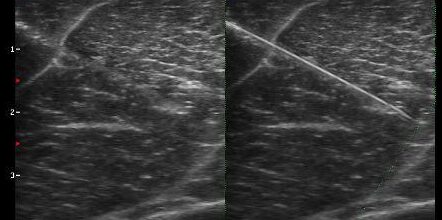

Imaging interventistico: le nuove frontiere Nel panorama dell’ecografia interventistica, uno dei temi più discussi negli ultimi anni è la visibilità dell’ago durante procedure come biopsie, drenaggi e infiltrazioni. A novembre 2025 è stato pubblicato uno studio che segna un passo avanti significativo in questo settore: “Real-time 3D Ultrasonic Needle Tracking with a Photoacoustic Beacon”, un progetto di ricerca che ha…